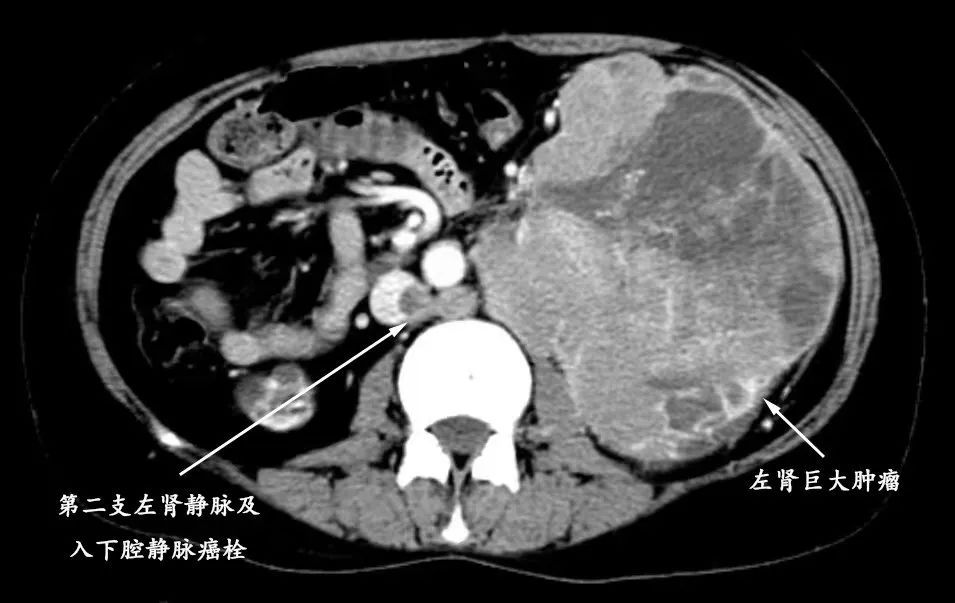

左图MRI可见下腔静脉内癌栓与巨大腹腔占位

邵远主任仔细阅片后,决定将患者收治入我院嘉定院区泌尿外科病房进行术前评估,同时在肾内科协助下规律透析治疗。我院检查发现,但女士肿物起源于左侧肾脏,体积达11*12.8*11.3cm,几乎填充整个左侧腹部(达T4期),推挤脾胃及同侧肠管。不仅如此,患者有两支左肾静脉,其主干及下腔静脉内均存在长段癌栓(将近Mayo Ⅲ级),一旦癌栓脱落,后果不堪设想。